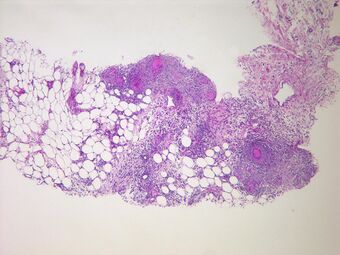

| Peritonitis from tuberculosis |

- Systemic infections (such as tuberculosis) may rarely have a peritoneal localisation.